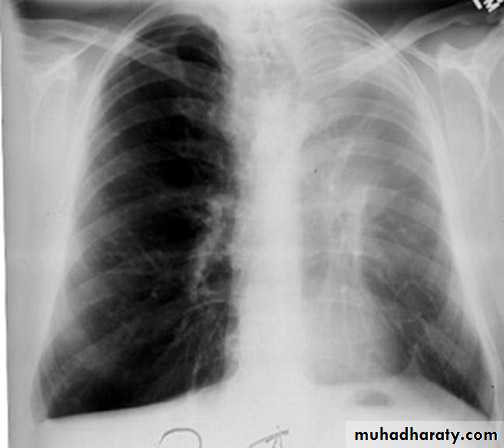

Radiopaque hemi-thoraxPneumothorax (air in pleural space )

Signs

Loss of vascular markings at the outer parts of lung fieldsDemarcating pleural line between the lung & vessels lacking area.

Well demarcating of the scapula

Epsilateral lung collapse

Tension pneumothorax

Emergency condition

Pressure effect on the mediastinum & major vessels

Treatment by chest tubes